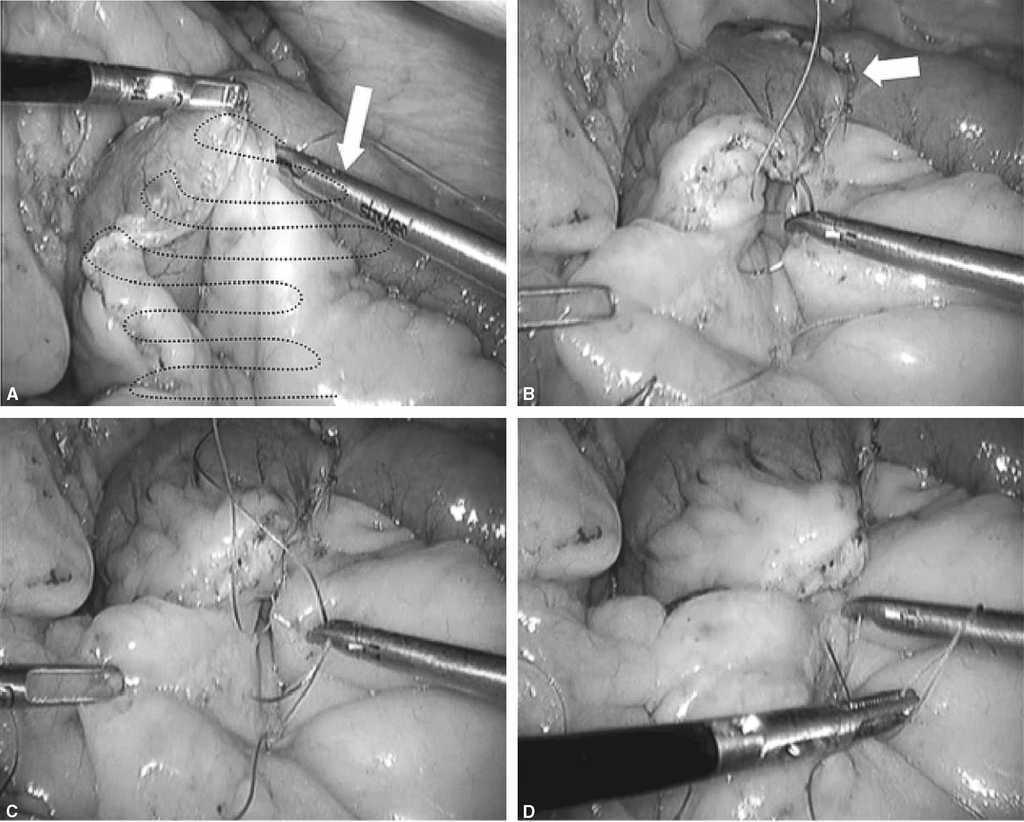

Fig. 7. A: identificamos la sutura 2 y preparamos el campo para comenzar la hemicorona desde el lado derecho al izquierdo hasta encontrarnos con la sutura 1. B: se realiza plicatura del meso con una sola pasada de la aguja y se asciende. Aquí estamos cerrando el espacio de Petersen desde el lado derecho del asa Y de Roux. C: se avanza hasta encontrar la sutura 1 en el punto medio, cogiendo serosa intestinal y grasa del mesocolon (cuadro blanco). D: cuando se realiza tracción del hilo (Ethibond®), se plica el meso cerrando el espacio de Petersen.

Fig. 8. A: como se indica en la figura, las 2 suturas se han encontrado en la línea media del defecto mesocólico. B: es el momento de anudar ambas suturas. C: es importante, como se indica en el cuadro blanco, no ejercer mucha tensión en el nudo de esta sutura porque se puede producir una obstrucción iatrogénica comprimiendo la salida del asa de Roux (hay que tener en cuenta que toda la sutura es continua y hay que ejercer la tensión apropiada para cerrar el espacio entre el orificio del mesocolon transverso y el asa Y de Roux). D: se ha anudado ambas suturas y se comprueba que no se ha afectado la salida del asa alimentaria en el mesocolon.